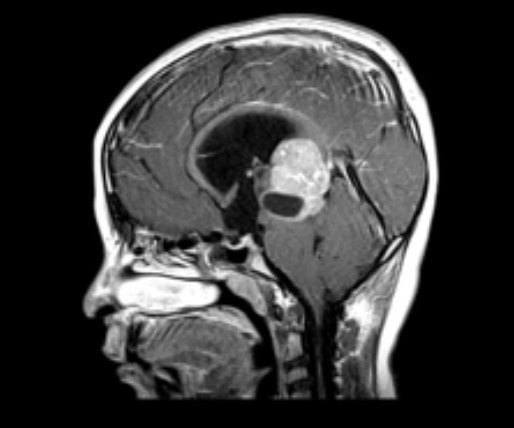

Pensar em Síndrome de Parinaud ou síndrome do mesencéfalo dorsal (principal causa = pinealoma)

Como caracteriza-se o nistagmo em see-saw?

Pensar em lesão na região anterior do III ventrículo Ex: Adenoma hipófise, craniofaringioma, Glioma de quiasma